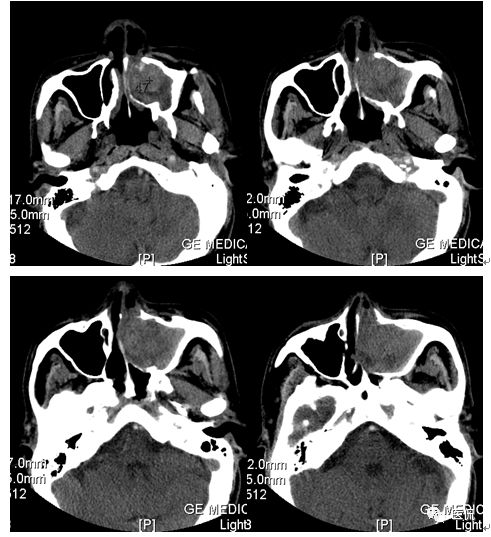

影像资料

男,73岁,以“左鼻塞流脓涕4个月”为主诉入院。诉缘于4个月前无明显诱因出现左鼻塞、流脓涕,伴左侧鼻腔嗅觉减退,偶有出血(2-3次)。鼻内窥镜示:鼻腔粘膜弥漫性充血肿胀,左侧鼻腔见一新生物完全充满其内,无空隙,表面附着清粘涕及少许血迹,右侧下鼻甲肥大,右侧中下鼻道狭窄,右侧鼻咽部光滑,右侧咽隐窝存在。

CT平扫及增强示:左侧上颌窦及鼻腔可见软组织密度影,呈膨胀性生长,周围骨质压迫性吸收破坏,累及左眶,病灶密度不均匀,周边区可见点状钙化,增动脉期轻度强化,局部见小灶性稍高密度区,静脉期病灶内见不均匀明显强化,CT值最高达117HU,延迟期强化范围有所增大。